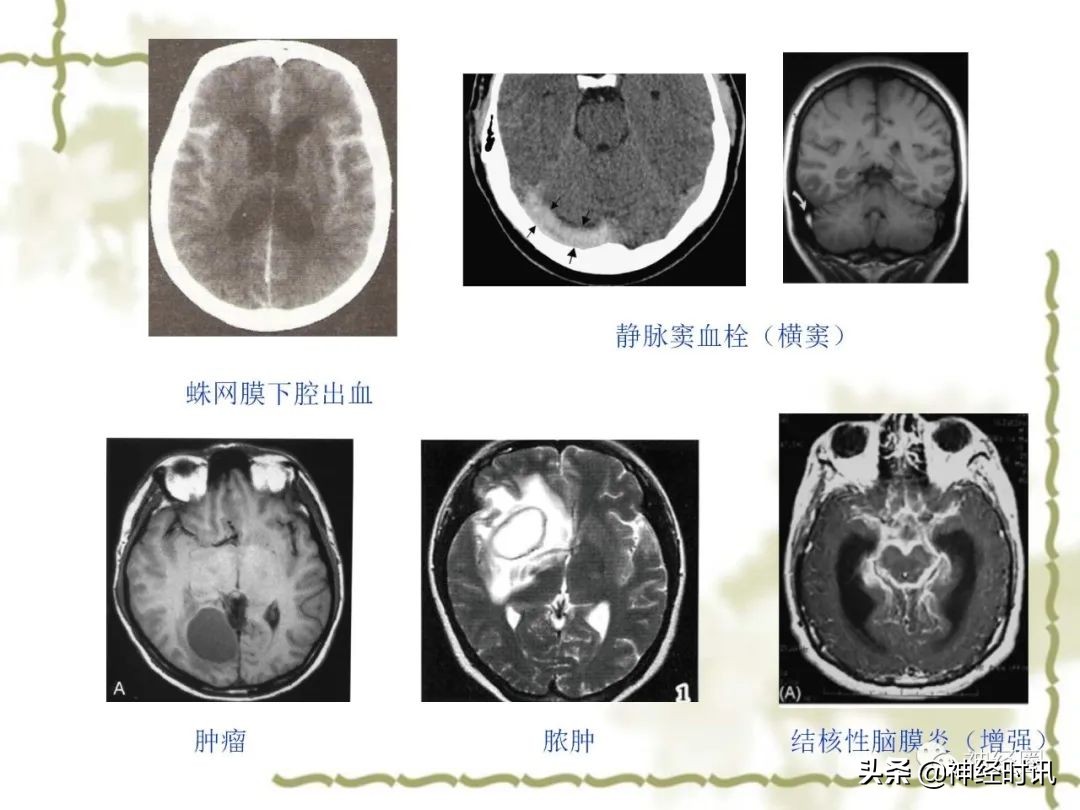

· 恶性头痛预警信号:

1、伴有视盘水肿、神经系统局灶症状和体征(除典型的视觉先兆外)或认知障碍;

2、突然发生的、迅速达到高峰的剧烈头痛(霹雳样头痛)

3、伴有发热;

4、成年人尤其是50岁后的新发头痛;

5、有高凝风险的患者出现的头痛;

6、有肿瘤或艾滋病史者出现的新发头痛;

7、与体位改变相关的头痛。

对于首次突发头痛、伴有神经系统阳性体征的头痛要高度怀疑器质性病变!